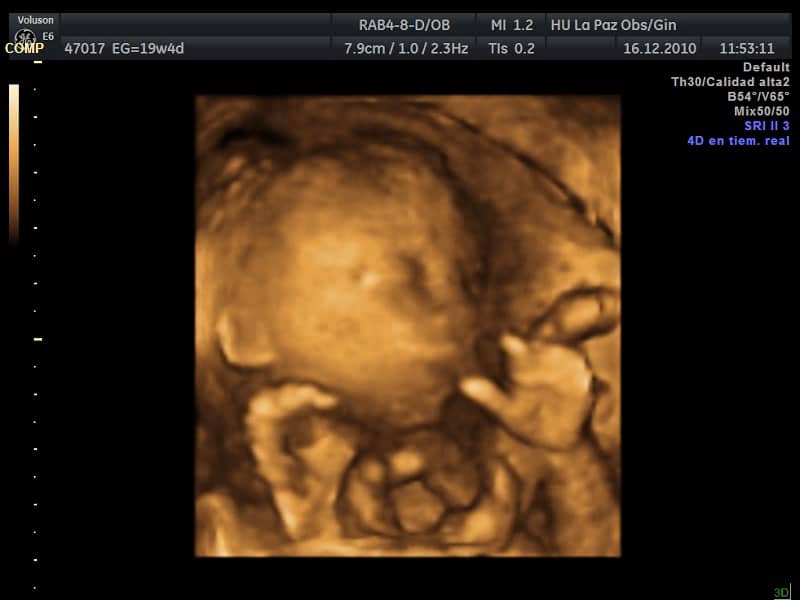

Ecografía de embarazo de 19 semanas. Durante la eco semana 19 de embarazo las medidas de tu bebé están en unos 15 cm y pesa aproximadamente 200 gramos. Semana 19 de Embarazo.

Ecografia 4d Embarazo De 19 Semanas Cara 4d Moviendose Dr Rafael Ortega Munoz Ciudad Real 19 Semanas De Embarazo Embarazo Diagnostico Prenatal

Ecografía Embarazo 2D y 3D Semana 20 - MALFORMACIONES FETALES. Cara de un bebé de 18 semanas. Durante la eco semana 19 de embarazo las medidas de tu bebé están en unos 15 cm y pesa aproximadamente 200 gramos. Hola tengo 19 semanas de embarazo de gemelas hoy tuve cita con mi ginecólogo y me dice que la ecografía muestra que una bebe está cabeza hacia abajo pero es muy pronto para que se acomode así a alguna de ustedes les ha pasado. Rafael Ortega Muñoz en la cual se aprecia un feto de 19 semanas cara http. Una semana más y superarás la mitad del tiempo de gestación. Durante estos días el cuerpo del bebé sufre muchos cambios a mejor y tú también notas transformaciones físicas como cambios genitales o palpitaciones.